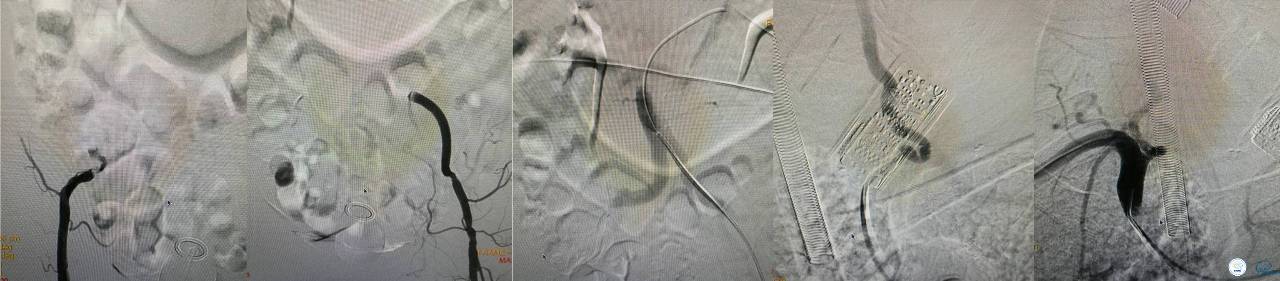

发病5.5小时给予股动脉穿刺

发现股动脉入路很差,考虑经桡穿刺。

》DSA资料(经桡动脉,5F导引导管)

》DSA资料(前2次取栓,未取出,soli 4-20)

》DSA资料(第3次取栓)

第3次取出血栓

》DSA资料(第3次取栓后,发病10h)